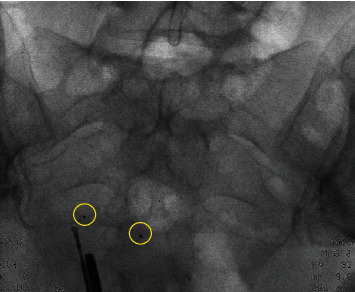

Figure 4.

Fluoroscopy during surgery. Two markers are visible.

Five weeks later, she returned for her postoperative control visit. Her abdominal pain was reduced, but still present. Also, she still experienced fatigue and was not satisfied. The doctor suggested that her complaints were probably not caused by Essure®. Due to persistent symptoms, she returned 17 months after the initial removal surgery. A flat panel abdominal X-ray was performed and showed two metal fragments. These were most likely to be parts of the removed Essure® devices. During initial laparoscopy, both fourth markers were visualized and removed, implying that these fragments were different parts of the device, supposedly the third markers (proximal marker of inner coil). The woman requested removal of these fragments. Six weeks later, hysteroscopy and laparoscopy were repeated. Hysteroscopically, no fragments of the devices were seen. During laparoscopy, intraoperative fluoroscopy was performed to visualize both remnants. The markers were bilaterally removed from the cornua, and this resulted in complete removal of the device remnants (Figures 4 and 5). The postoperative period was uncomplicated. Six week later, the woman continued to do well. Her symptoms were reduced; she only continued to experience symptoms of her left groin.